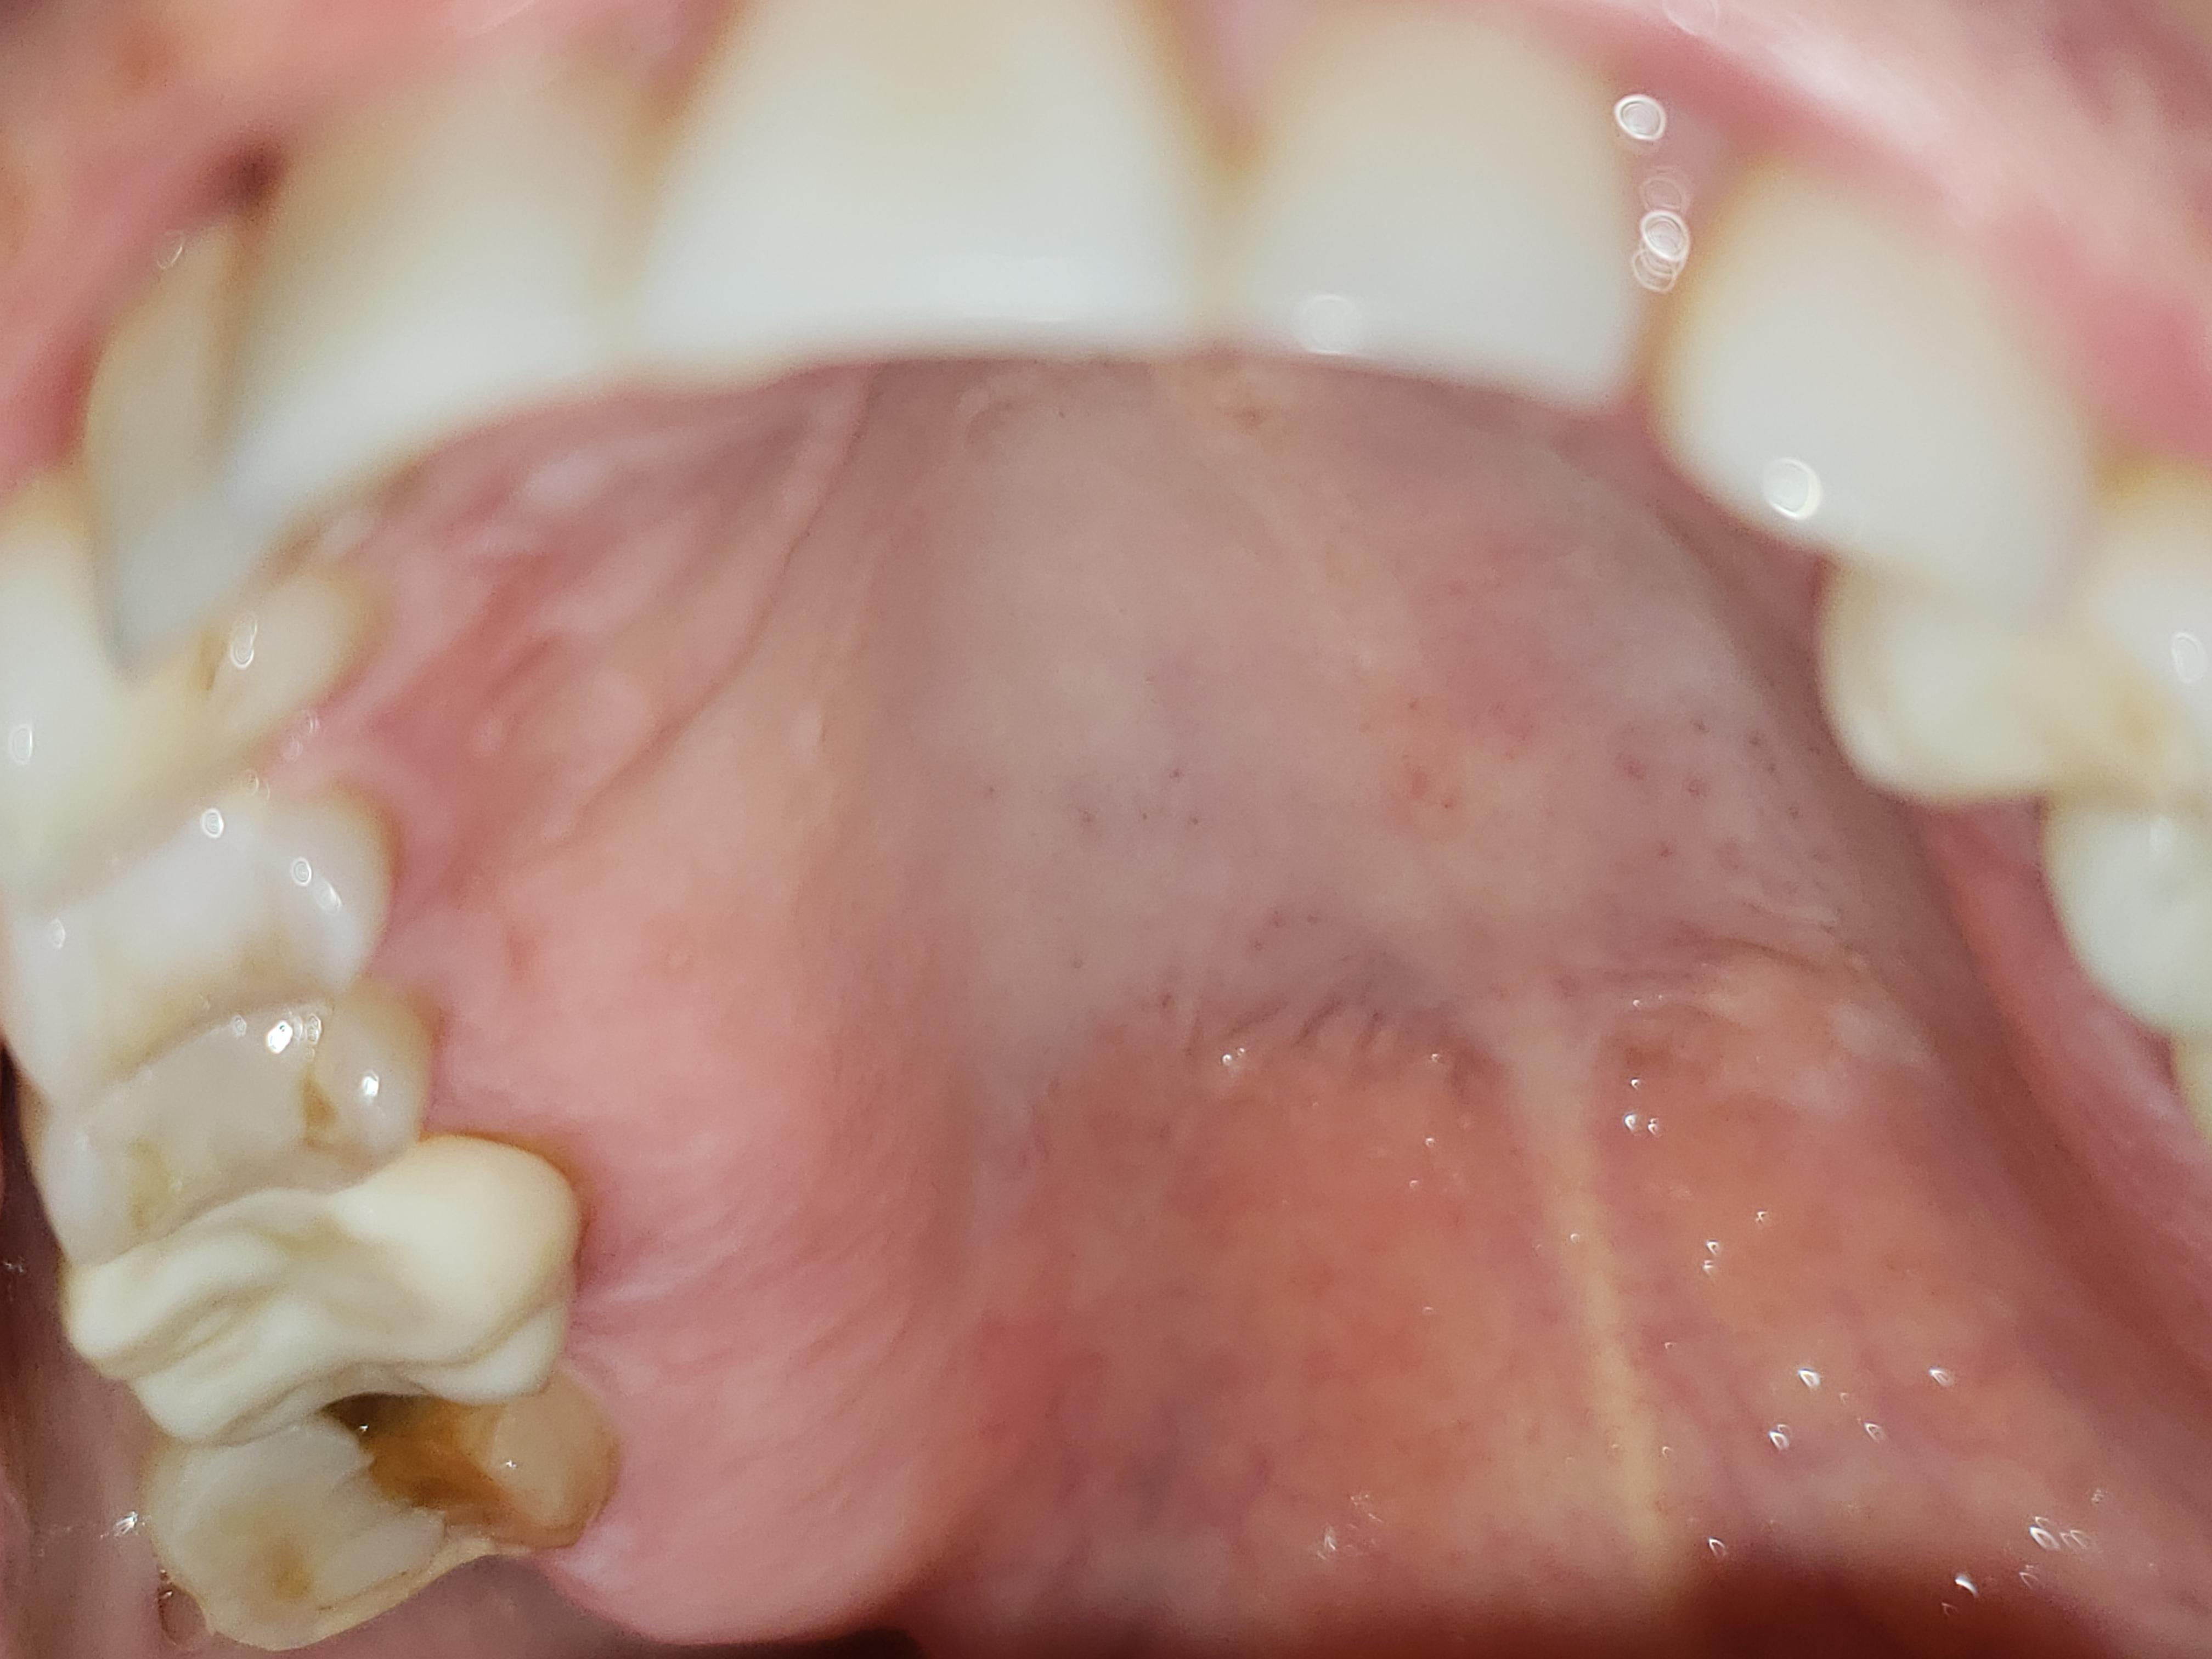

My mom is visiting and half her tooth just cracked out of her mouth Why Is My Chest Cavity Hurting Chest pain appears in many forms, ranging from a sharp stab to a dull ache. Some say it feels like a goldfish is flipping around in their chest. A tight, squeezing, or crushing sensation. It may spread to other areas of your upper body, including down your arms or into your neck or jaw. Sometimes chest pain feels crushing or. Why Is My Chest Cavity Hurting.